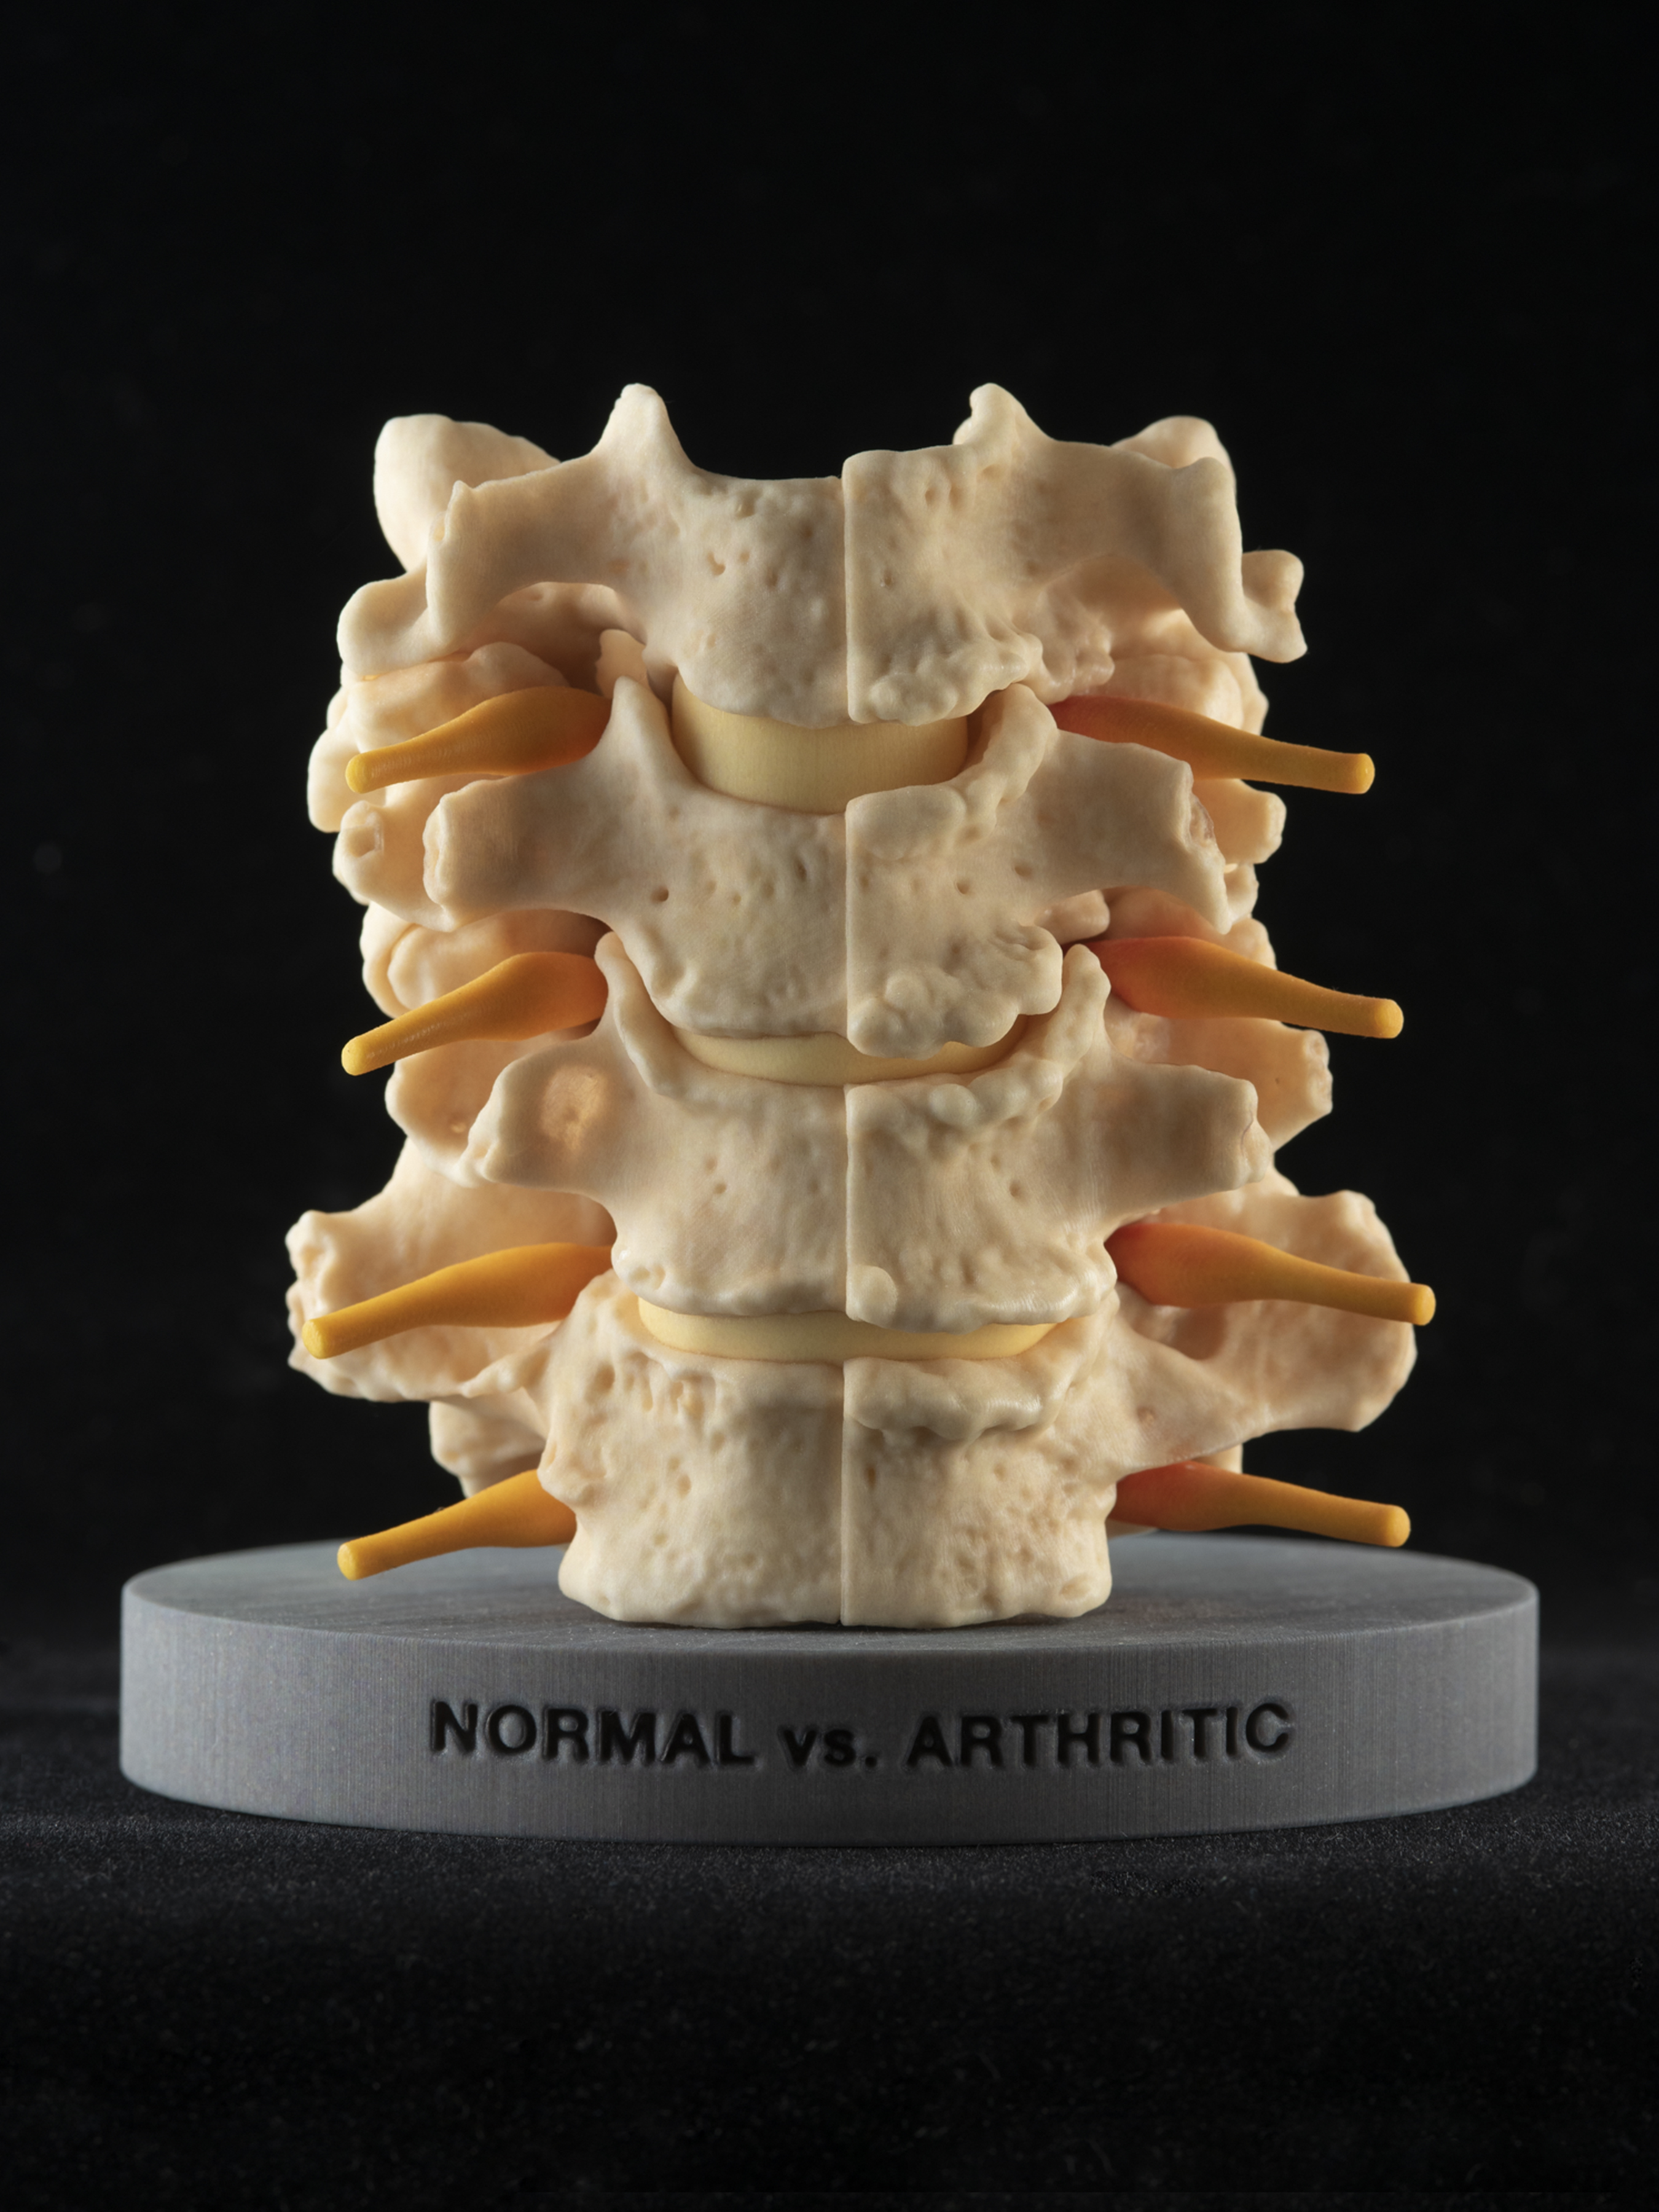

- Plastinated specimen Lab – sample specimens infused with plastic (no movement, no interactivity, details such as nerves are poorly preserved)

- Plastic model Lab – plastic shaped like organs